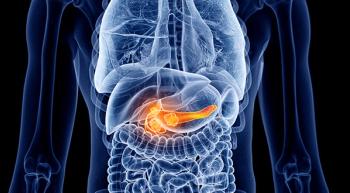

Significant weight loss, increased blood glucose levels, and older age at onset of diabetes may be useful in determining the risk of pancreatic cancer in people newly diagnosed with diabetes.